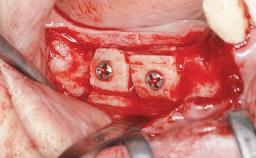

A 56-year-old woman presented for treatment with complete edentulism of the maxilla. She had been using a complete removable denture since she was relatively young (age 30). Her chief complaint at presentation was lack of retention of the upper denture and a desire for a better restoration in order to improve retention, function, and esthetics. An initial clinical examination showed that the anterior maxilla was moderately atrophic both horizontally and vertically, also revealing a vertical deficiency of the posterior alveolar process. The mandible included natural teeth from 45 to 35, with previous extrusion of the anterior teeth that was being orthodontically treated. Also, there were two external hexagon dental implants at sites 46 and 36 that had been inserted elsewhere at a previous point in time. As the conditions in the mandible were healthy, including the teeth and the two implants, the patient had no complaints there.

Bone Augmentation | Horizontal|Sinus Floor Elevation|Staged |

Augmentation Materials | Autogenous chips|Autogenous block(s) |